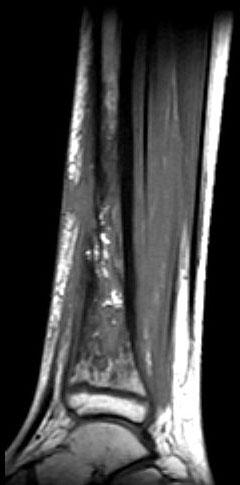

问题 男,33岁,有发热,小腿局部有疼痛,红肿并有压痛,请结合图像,选择最佳答案 ( )

选项 A、骨髓瘤 B、骨化性肌炎 C、脂肪瘤 D、未见异常 E、骨髓炎

答案 E